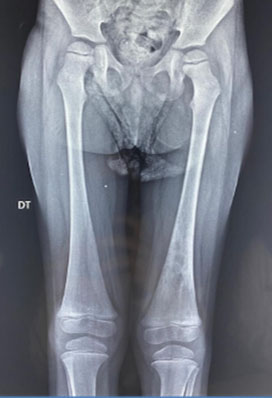

To gain further insight into the extent and nature of the skeletal abnormalities, magnetic resonance imaging (MRI) was performed. The MRI scans demonstrated multiple bilateral signal anomalies in the diaphyseal and metaphyseal regions of the femurs. These anomalies appeared as areas of low signal intensity on T1-weighted images and exhibited high signal intensity on short tau inversion recovery (STIR) images. Notably, the infarcted zones were delineated by a map-like serpiginous border, serving as a distinct visual marker of the affected areas (Figure 2A, Figure 2B, Figure 2C).

Figure 2: A–C: MRI of the femurs in the coronal plane, in A T1W and in B STIR, and in C T2W FS of the knees, showing multiple femoral bilateral diaphysio-metaphysis signal anomalies with low signal in T1W, high signal in STIR, circulated by a serpiginous line in geographic map delineating the infarcted zone. This is combined with an enlarged and plated aspect of the lower femoral and tibial metaphysis, realizing the Erlenmeyer flask deformity.